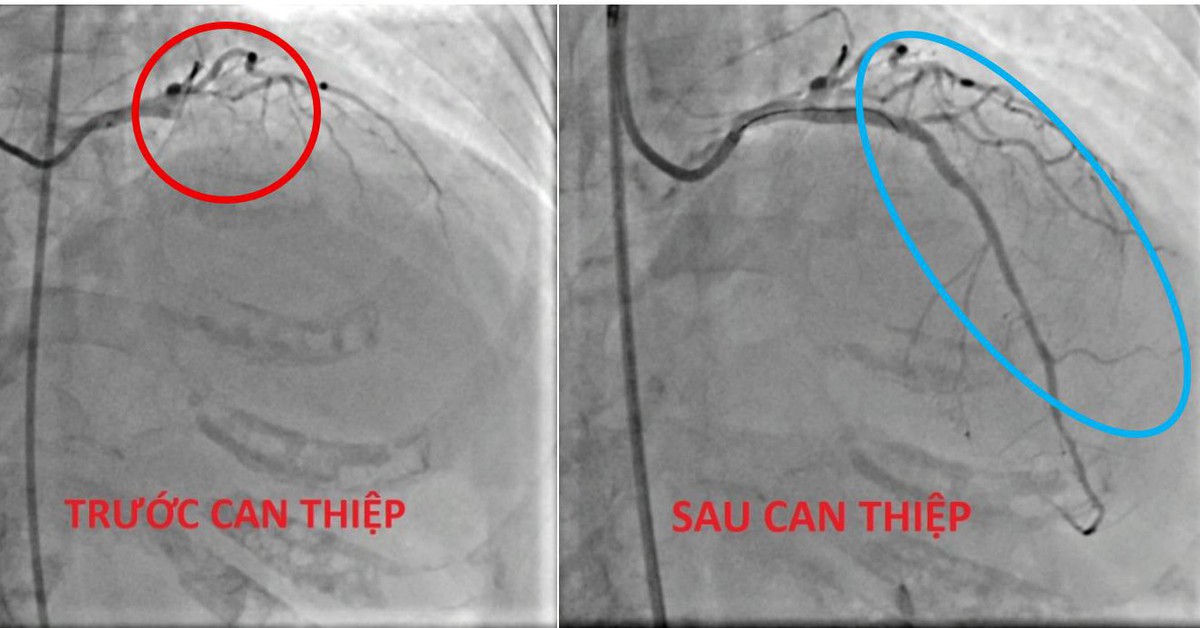

Hình ảnh chụp mạch vành cho thấy tổn thương nặng nề và phức tạp: nhánh động mạch liên thất trước (LAD) - đóng vai trò cung cấp máu cho thành trước và vách liên thất - bị tắc ngay tại vị trí lỗ vào do huyết khối lớn. Đồng thời, ghi nhận hẹp đáng kể tại thân chung động mạch vành trái (Left Main), làm gia tăng nguy cơ thiếu máu cơ tim lan rộng và tử vong sớm nếu không được tái tưới máu kịp thời. Ngoài ra, vôi hóa lan tỏa tại thành mạch càng làm phức tạp hóa quá trình tiếp cận và can thiệp tổn thương.

Sau một thời gian ngắn, thủ thuật tái thông đã được thực hiện thành công, khôi phục dòng máu nuôi tim, góp phần cứu sống người bệnh.